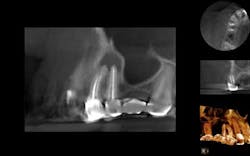

Ten days later, the patient returned asymptomatic. Again, after proper anesthesia and isolation the temp filling was removed, additional irrigation, along with cleaning and shaping of the canals was continued, the case was obturated, and a permanent seal placed that day. The patient reported for a 14-month follow-up and a subsequent CBCT image was obtained (Fig. 7). The sagittal view shows complete boney healing of the previous periapical lesion, and retention of the fixed prosthesis.

Fig. 7: CBCT sagittal view (Nos. 4 and 5) 14-month postop, showing complete resolution of the apical lesion with intact lamina dura